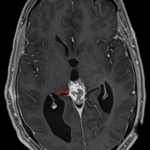

MRI

- Avidly, somewhat heterogeneously enhancing pineal region mass measuring 2.7 x 2 x 3 cm which engulfs the pineal calcification and exerts downward mass effect on the tectum resulting in obstructive hydrocephalus

- Mild corresponding T1 signal hypointensity

- T2 signal intensity and restricted diffusion are similar to gray matter

- Left frontal approach ventricular drainage catheter